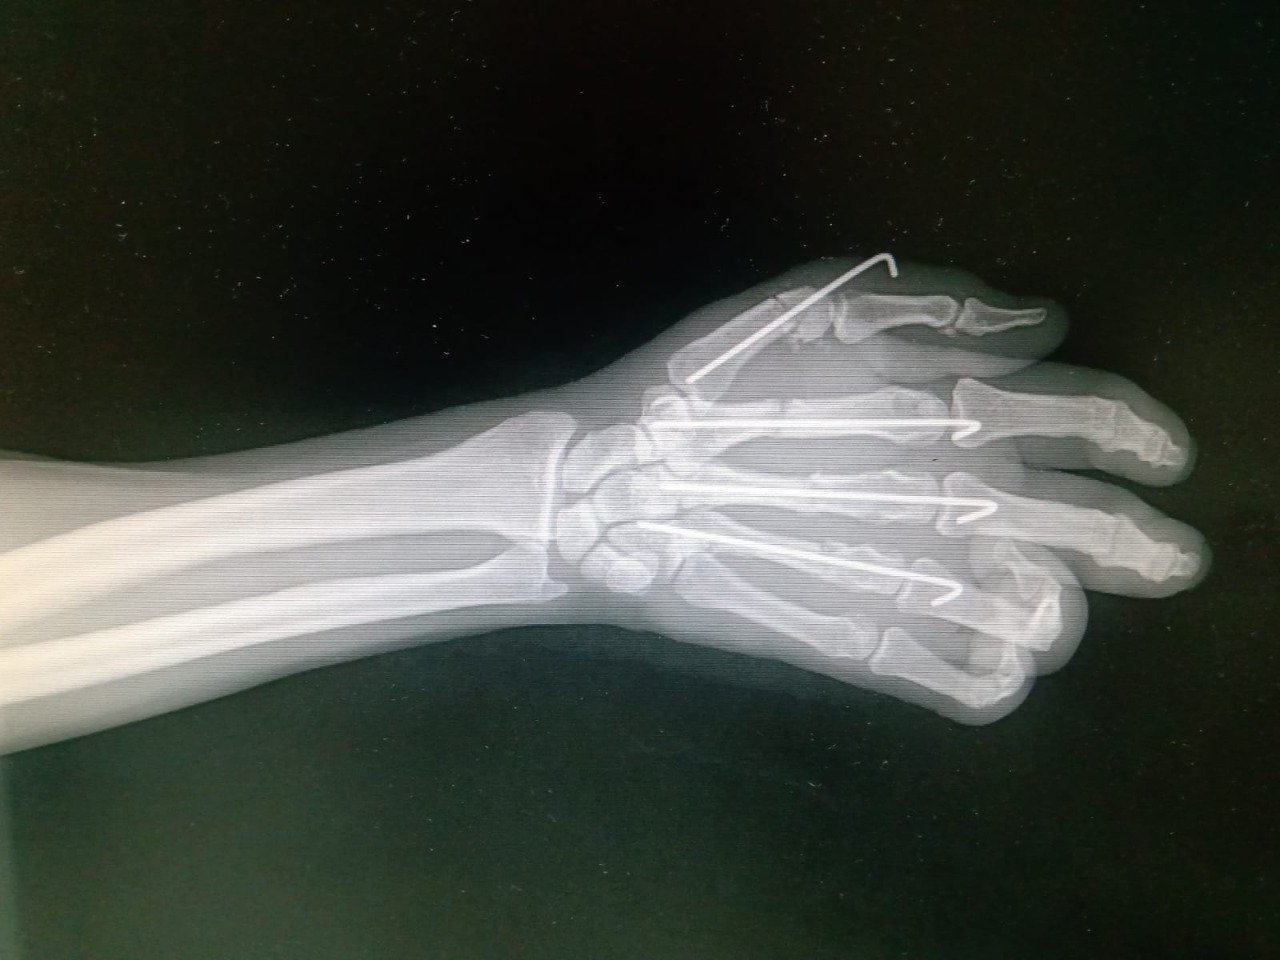

“Dos días después del accidente, el sábado, me llevaron a quirófano. Fue una operación muy larga, más de cuatro horas; me pusieron cinco clavos y lograron salvar mi mano”, recuerda Horlando.

Johana Ocampo Villalobos, traumatóloga ortopedista del IMSS, informó que se logró la reconstrucción ósea y la reparación vascular, nerviosa y de tendones para salvar la extremidad.

Horlando ha regresado al quirófano en dos ocasiones, una de ellas para realizar un exitoso injerto de piel. El tratamiento recibido ha dado pie a una recuperación notable, que permitió el retiro de los clavos dos semanas antes de lo programado.